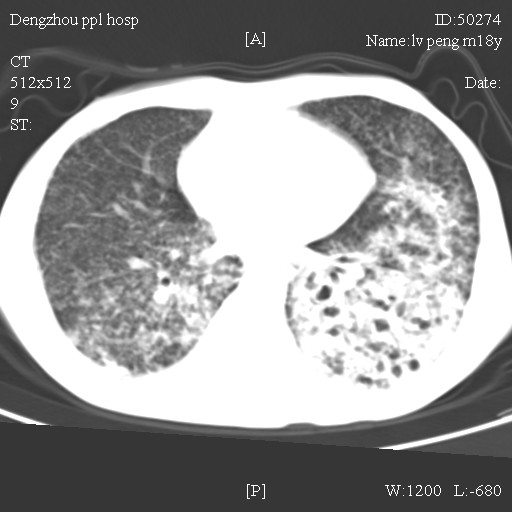

标题: CT10510:男.18岁,咳嗽咳痰两月.(有病理) [打印本页]

标题: CT10510:男.18岁,咳嗽咳痰两月.(有病理)

双肺布满大片状实变及网格状结节影,内参杂大小不等的气囊及空气支气管征,心脏增大。考虑:1 全身结缔组织疾病—系统性红斑狼仓?2 肺泡蛋白沉积症合并感染!

双肺布满大片状实变及网格状结节影,内参杂大小不等的气囊及空气支气管征,双侧胸膜腔少量积液,双下肺近膈面透亮度尚可,病人较年轻,病变较重(不知为什么上胃管?)考虑:1.胶原病肺部改变,2.组织细胞病x。结合实验室检查。

首先考虑组织细胞x病。两肺中上肺野多发囊腔,中下肺野内见多发小结节,并可见肺间质增厚。患者是男性,年龄较小。胶原性病变比较多见的类风湿、系统性红斑狼疮和硬皮病临床和影像均不是很支持,类风湿和系统性红斑狼疮的肺部表现最常见的是胸腔积液,硬皮病可见食管的扩张。

肺内多发斑片状、结节状、融合大片状及网格状影,多发薄壁空腔影,胸膜肥厚,纵隔、气管右移,考虑ⅲ型肺结核,多发空洞,继发肺间质纤维化。

双肺结核并播散.患者以肠梗阻入院,手术为肠结核.术后咳嗽做ct检查.